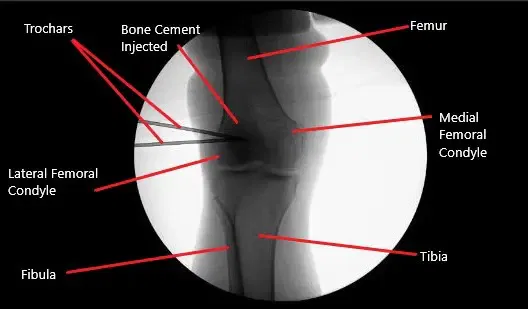

Intraoperative fluoroscopic image of the right knee showing tricalcium phosphate bone injection.

Tricalcium phosphate bone cement was mixed and injected about 2.5 milliliters into each cannula and trochar was introduced. Pictures were taken in the C-arm and found cement to be into the bone only. An arthroscope was entered to examine the femoral condyle as well as the intercondylar notch and no bone cement could be seen extravasating there.

The knee scope was removed and the knee was drained completely. The cement was left to set. Once the bone cement was set for more than 12 minutes, the cannula was removed. The final picture was taken with the fluoroscope and saved. The knee was thoroughly drained and the wound was washed.